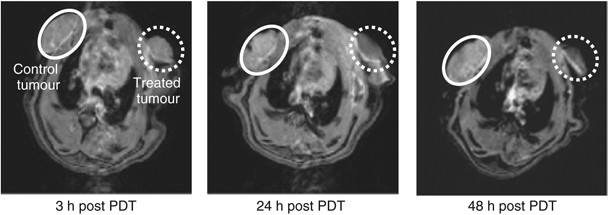

The MRI was employed to further assess effects of ADPM06-induced PDT on tumour vascular perfusion. Immediately after dynamic PET acquisition (∼3 h post treatment) as described above, 0.6 ml of MRI contrast agent (Gd-DTPA) was injected i.v. at 0.6 ml min−1 and MRI scans were performed at ∼3, 24, and 48 h after treatment. The evident difference in accumulation of contrast agent between control and PDT-treated tumours is indicative of an overall decrease in vascular perfusion, as well as a decrease in perfusion over time. These data are also consistent with a vascular-targeting effect following immediate light irradiation after i.v. administration of the photosensitiser (Figure 5).

MRI approach to assessing vascular-targeting effect in vivo. The MRI of control 13762 MAT B III rat tumour (white circle) and PDT-treated tumour (0.8 mg kg−1 ADPM06+150 J cm−2 light) (dashed white circle) at ∼3, 24, and 48 h post-treatment with a Gd-DTPA injection, illustrating the change in tumour perfusion.